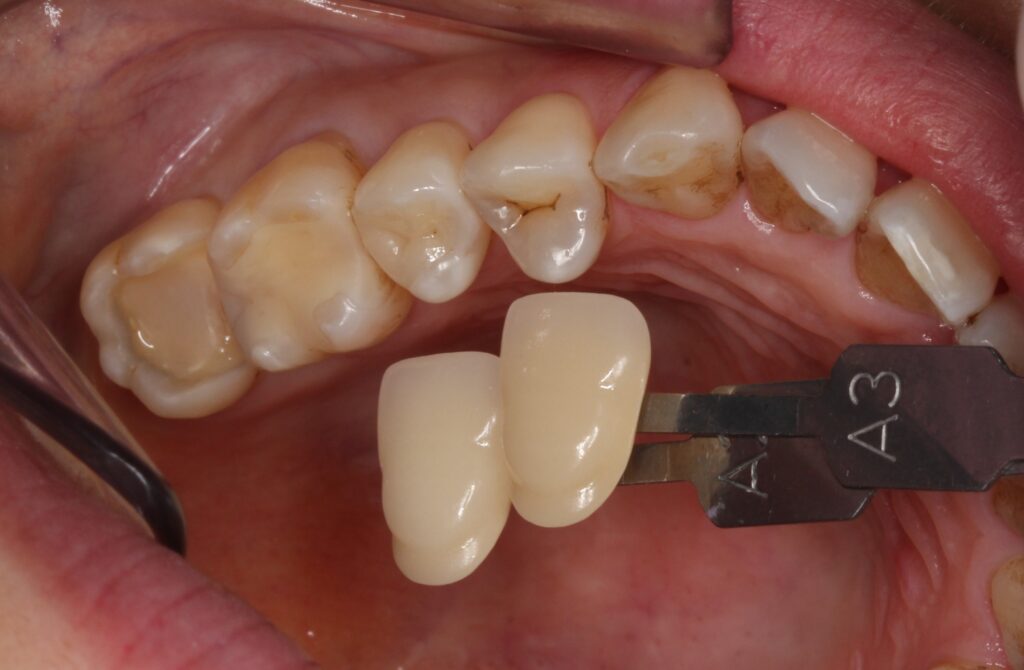

お口の中を見てみると、

このような状態です。

今回の歯はこちらの青枠の歯ですね。

他の歯にも詰め物が入っています。均一な黄色みがあり、歯と浮いた感じに詰められているため、ハイブリッドセラミックという材料だと推測が出来ます。

歯の色見本で歯の色を記録して、セラミックインレーを製作します。